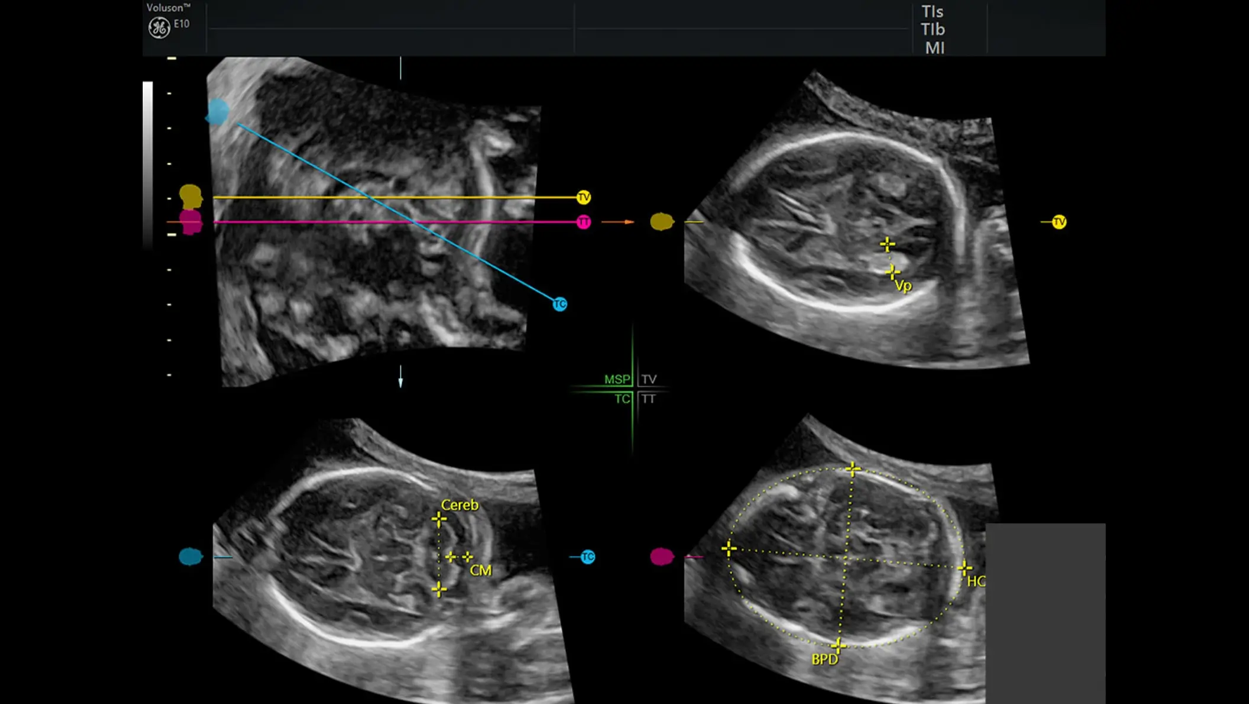

Menos tiempo colocando cursores, más tiempo interpretando.

Identifica anatomía automáticamente y ayuda en etiquetado y mediciones.